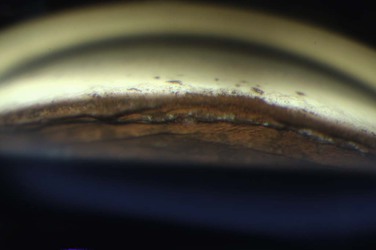

Patients are treated with antiglaucoma medications and frequent topical steroids. When the inflammation subsides, the medications are then slowly tapered off within a month. Occasionally, a release of aqueous through the paracenteses at the slit lamp may be performed if a high IOP rise occurs. Gonioscopy typically reveals opening of the angle structures with irregular pigmentation on the newly exposed trabecular meshwork and the angle wall (Fig. 108-6). Angle recession or a cyclodialysis cleft are undesirable findings. If successful, anterior segment optical coherence tomography or ultrasound biomicroscopy should demonstrate separation of the PAS and reopening more than half of the entire angle (Figs 108-2, 108-7).